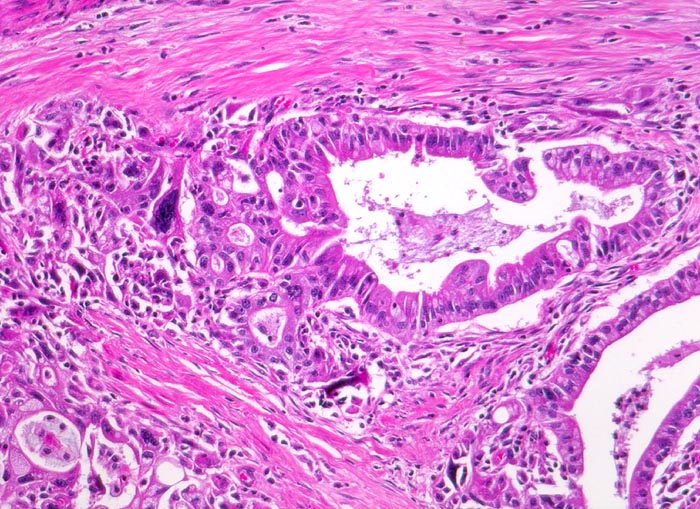

Morphologische Merkmale:

• Unregelmässige Anordnung der Drüsen (keine Läppchenarchitektur erkennbar).

• Kribriforme Drüsenformationen.

• Inkomplette Drüsen mit unvollständigen Lumina und Infiltration des Stromas durch Tumoreinzelzellen.

• Nekrotische Tumorzellen in den Drüsenlumina.

• Ausgeprägte Polymorphie und Hyperchromasie der Tumorzellkerne.

• Desmoplastisches Stroma.

• Rechts oben Reste von nicht neoplastischem Pankreasparenchym mit fokaler chronisch obstruktiver Pankreatitis als Folge von tumorbedingten Gangobstruktionen: Vollständige Atrophie des exokrinen Pankreas bei erhaltenen Inseln. Ersatz des atrophen Parenchyms durch Fibrose. Chronisches Entzündungsinfiltrat.